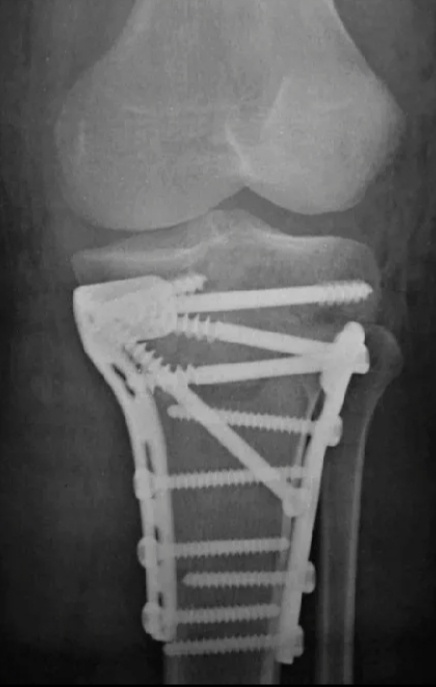

Ушла в оперу, собирали большую берцовую(тот самый зловредный мыщелковый перелом) на пластины.Случай непростой, на две пластины собирали Это не слишком долгая операция и в начале десятого я освободилась.

Пришлось идти. Ага, тот самый, с берцовой, которому поставили пластины.